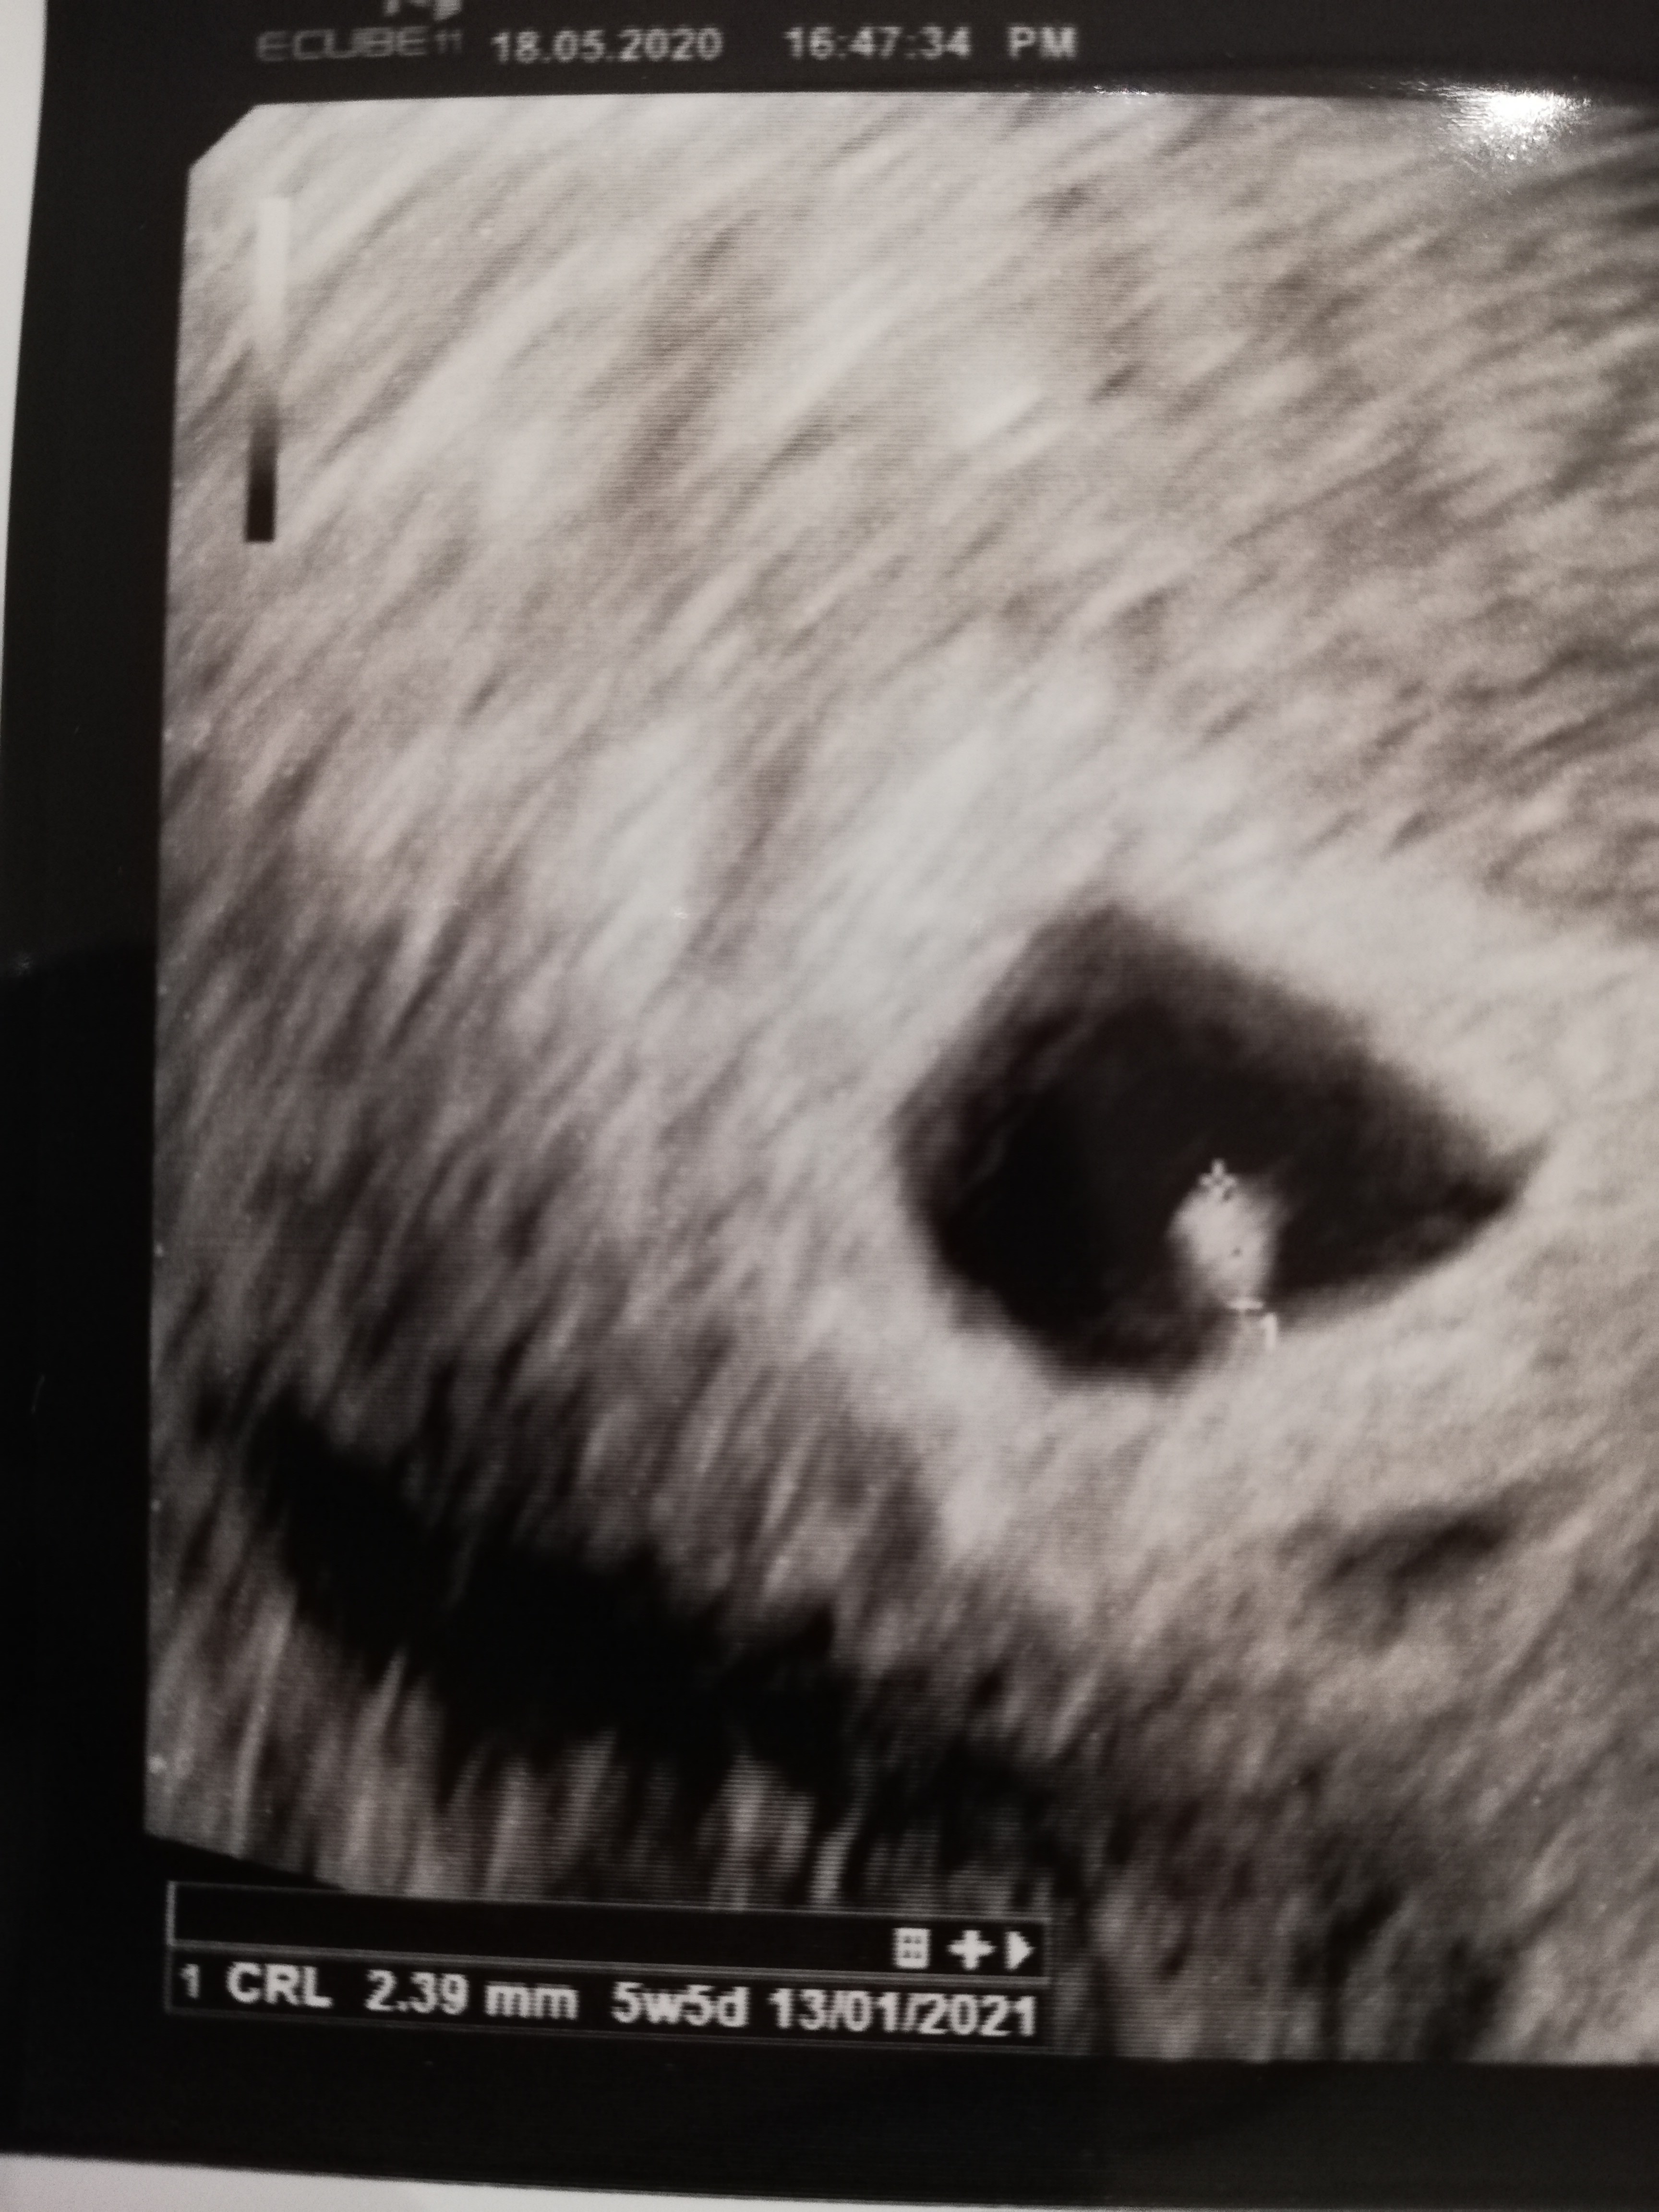

Hej dziewczyny, jestem po wizycie :) Kropeczek rośnie, ma AŻ 2,39 mm! :D lekarz powiedział że wszystko w porządku, serduszko bije, ale jest za wcześnie żeby robił dopplera i tu mała zmiana, na poprzedniej wizycie wg usg był to 4+6 i nie było widać jeszcze zarodka, dzisiaj 5+5 (po 2 tygodniach) :) termin przesunięty z 5 na 11 stycznia. Ze względu na tsh o którym wcześniej pisałam 2,93 mam przepisany Euthyrox, do późniejszej kontroli. Kolejna wizyta 8 czerwca :D Ulżyło mi po dzisiejszej wizycie, trochę kamień z serca spadł. Trzymam kciuki, za jutrzejsze wizyty i dajcie znać jak poszło

Załączniki

• IMG_20200518_223814.jpg

IMG_20200518_223814.jpg

1,9 MB · Wyświetleń: 114